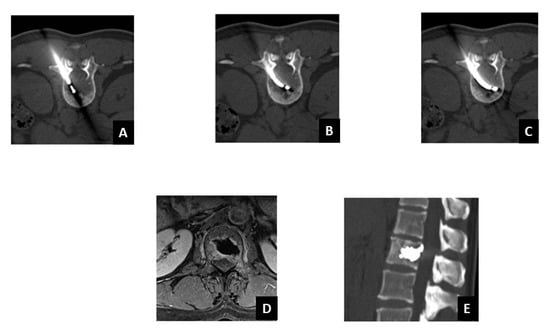

Figure 2. Advantages of the use of the navigational radiofrequency ablation device using steerable needles instead of conventional straight ones. L2 breast cancer metastasis (same patient from Figure 1). (AC) Placement of targeted radiofrequency ablation device to obtain complete necrosis of the tumor lesion located in a difficult-to-access location. (D,E) Follow-up imaging after one month after the tRFA-VA treatment. (D) MRI showed a layer of granulation tissue around the ablated zone. This is the typical inflammatory reaction after tRFA ablation. (E) CT scan showed the right position of the polymethylmethacrylate used for VA. After tRFA, vertebroplasty was performed to strengthen the bone in order to avoid pathological fracture.